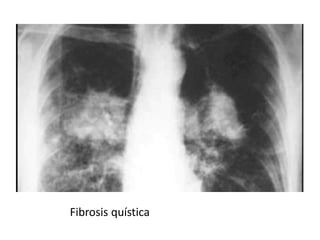

Fibrosis quística